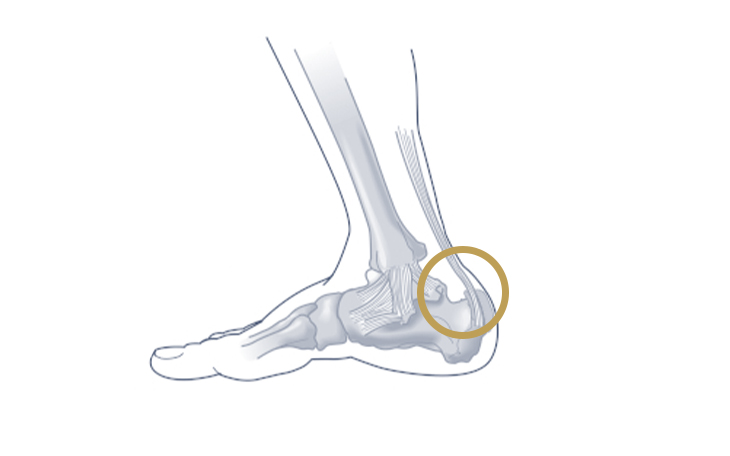

Symptome

Beim anterioren Impingement treten Schmerzen an der Vorderseite des Sprunggelenks auf, insbesondere bei Dorsalextension (Anziehen des Fußes). Beim posterioren Impingement treten Schmerzen an der Rückseite des Sprunggelenks auf, insbesondere bei Plantarflexion (Strecken des Fußes).

Ursachen

Häufige Ursachen sind wiederholte Mikrotraumata, Verletzungen, Knochenanbauten (Osteophyten) oder freie Gelenkkörper.

Konservative Therapie

Entlastung, Kühlung, entzündungshemmende Medikamente, Physiotherapie zur Verbesserung der Beweglichkeit und Kräftigung der Muskulatur sowie Injektionen mit Kortikosteroiden können die Beschwerden lindern.

Operative Therapie

Wenn die konservativen Maßnahmen nicht ausreichend helfen, kann eine Operation in Erwägung gezogen werden. Dabei wird das eingeklemmte Gewebe in der Regel arthroskopisch entfernt.